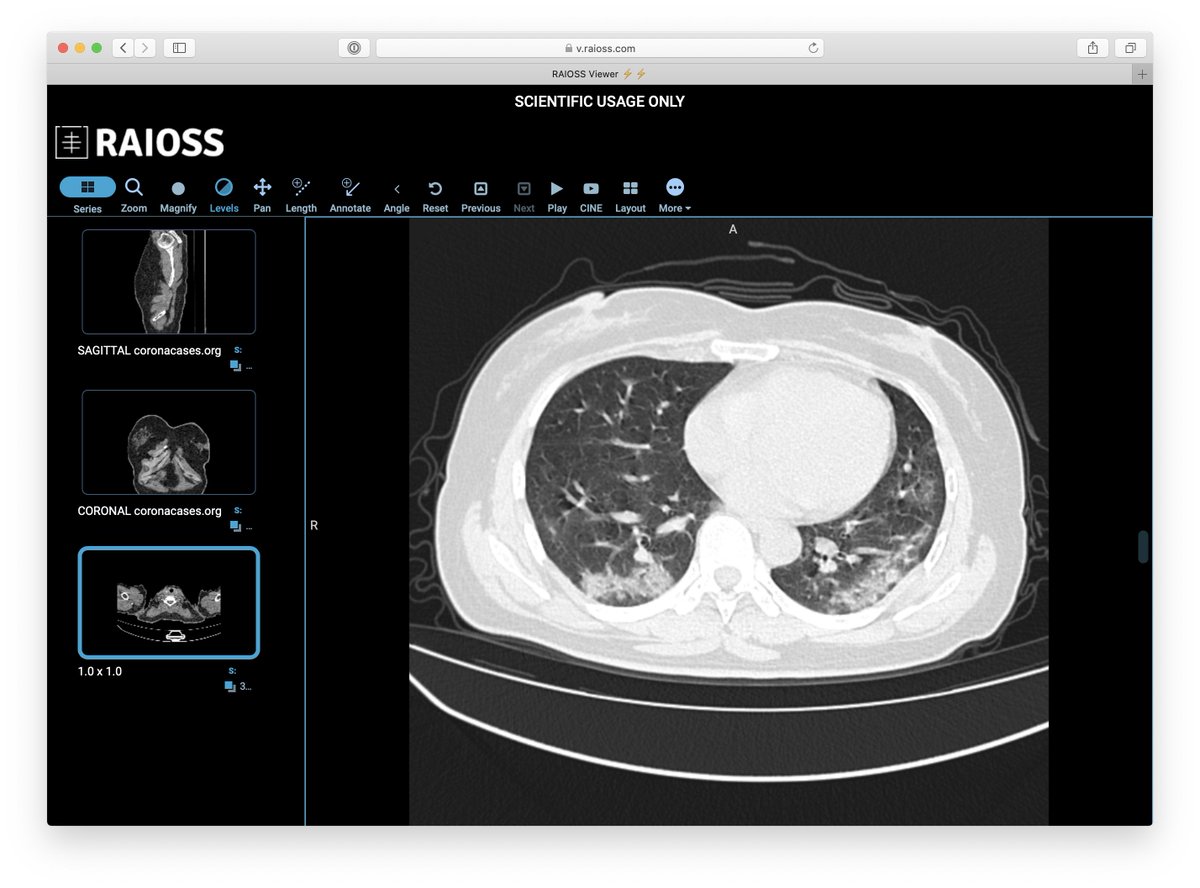

It’s important for us to recognize the various patterns of #COVID19 on CT, but as @thoracicrad and @RadiologyACR have stated, CT should NOT be used as screening. #FOAMrad #FOAMed

@thoracicrad

Society of Thoracic Radiology

6 years

To help familiarize radiologists with the chest CT appearance of #COVID19, RAIOSS & Livon Saúde have begun publicly sharing complete chest CT stacks (scrollable, window/level-able) of confirmed cases for educational and training purposes. https://t.co/5jVbEQQnzE